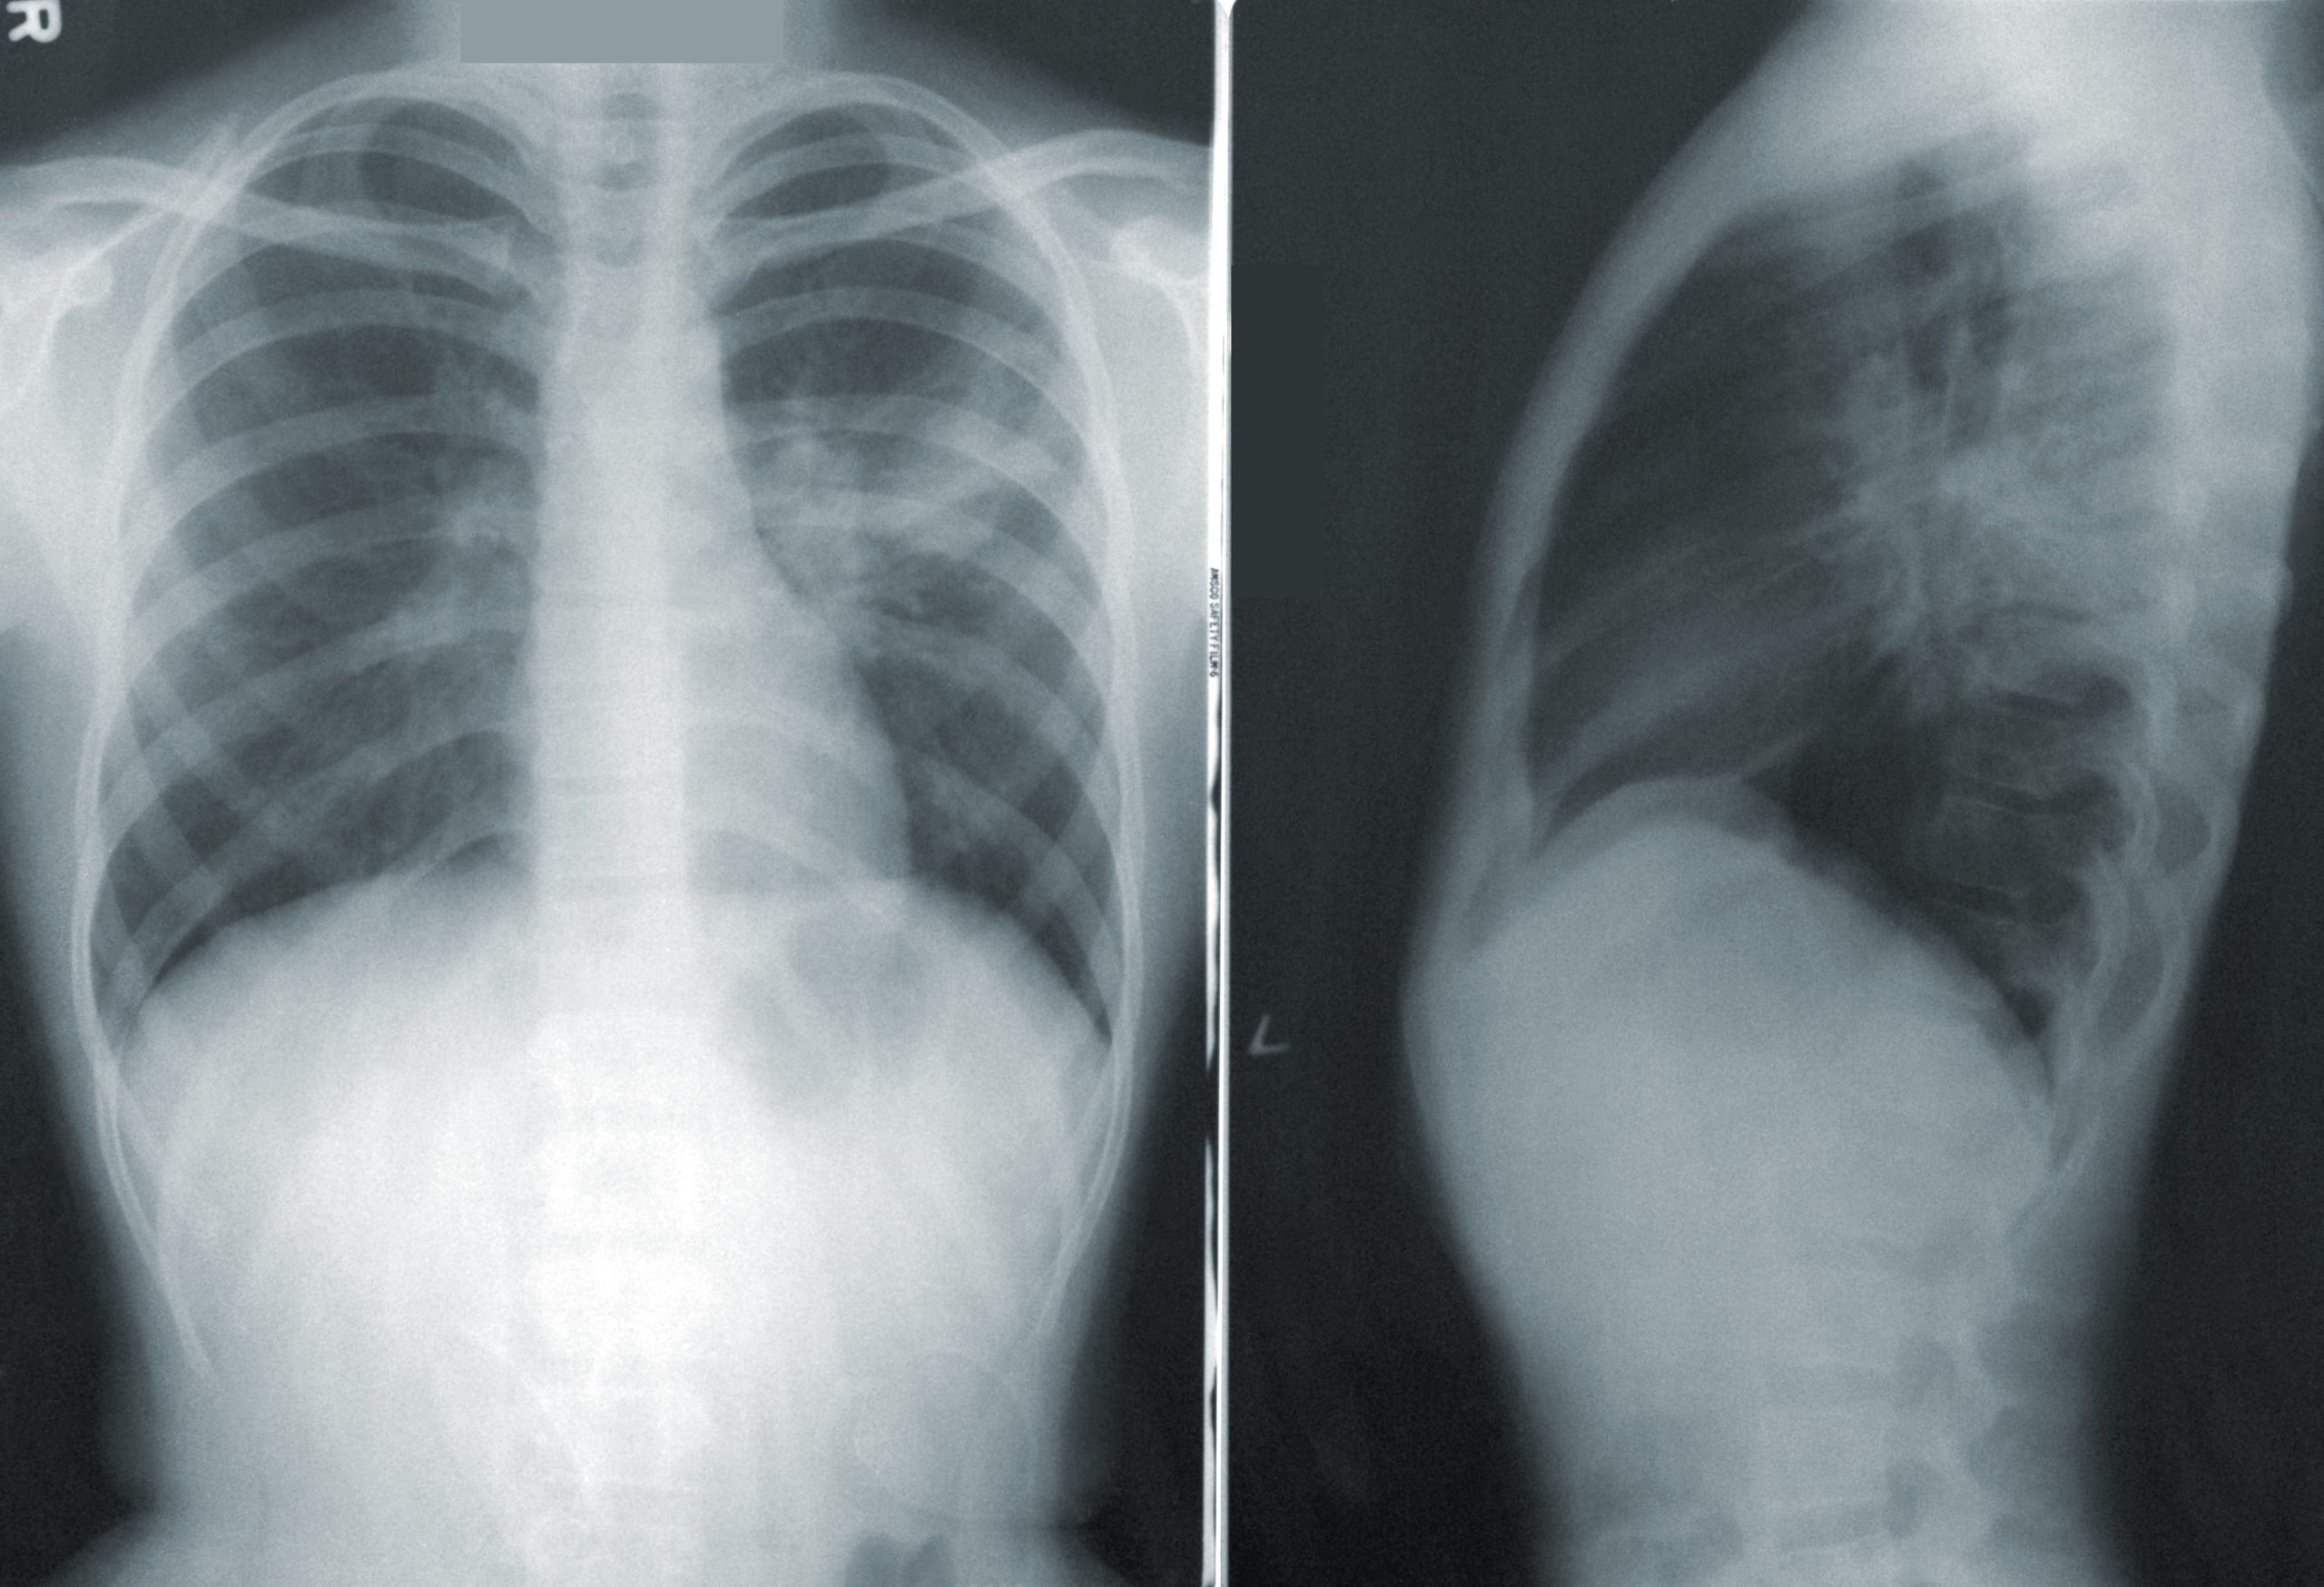

Πρόσφατα ανακαλύφθηκε ότι ένα 7χρονο κορίτσι στην Παραγουάη είχε ένα καπάκι οδοντόκρεμας κρυμμένο μέσα στον πνεύμονά της, ενώ υπάρχουν κι άλλες, πολλές, περίεργες ιστορίες αντικειμένων που παρέμεναν μέσα στο αναπνευστικό σύστημα για χρόνια και κανείς δεν το είχε παρατηρήσει.

«Ένας ταχυδρόμος από το Πρέστον της Αγγλίας, εισέπνευσε ένα εξάρτημα από Playmobil ως παιδί, αλλά ανακαλύφθηκε μόνο όταν ο 47χρονος έκανε ακτινογραφία στους πνεύμονες όταν παρουσίασε επίμονο βήχα», είπε ο Τέιλορ. «Ενώ δεν υπήρχε για 40 χρόνια ως εύρημα, ένας άνδρας εισέπνευσε ένα μπιζέλι, το οποίο βρισκόταν στη θέση του για αρκετό καιρό ώστε να αρχίσει να φυτρώνει στην αναπνευστική του οδό».